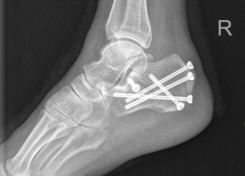

在骨科中心主任吴超的带领下,团队采用了天玑Ⅱ骨科手术机器人为程某开展了微创手术治疗,该手术时间短、创伤小、出血少、透视次数少,同时实现了骨折块的解剖复位和精准的螺钉置入及固定;术后影像学显示患者关节面完全复位,螺钉位置良好,固定可靠。